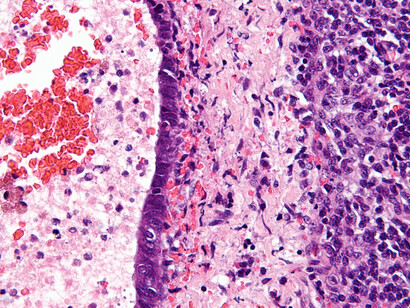

Endometriosis

Si al bajar el período te duele tanto que tienes que parar tu vida unos días cada mes, algo no va bien. ¿A ver si te sientes identificada? Tienes un malestar intenso con dolores punzantes en el abdomen, espalda baja y pelvis, y síntomas como la fatiga, problemas intestinales y cambios en los patrones de menstruación. ¿Sí? Pues eres candidata a sufrir endometriosis.

Es una enfermedad que padecen entre un diez y un quince por ciento de las mujeres. Como ves, es más habitual de lo que parece y le puede pasar a cualquiera de nosotras.

Se produce cuando el revestimiento del útero (el endometrio) es muy rebelde y decide crecer en lugares donde no debería, como en los ovarios, las trompas de Falopio e incluso en otros órganos. Al llegar la regla, estos tejidos "rebeldes" también sangran y causan dolor, inflamación y, en algunos casos, la formación de tejido cicatricial (llamado tejido fibroso o adherencias).